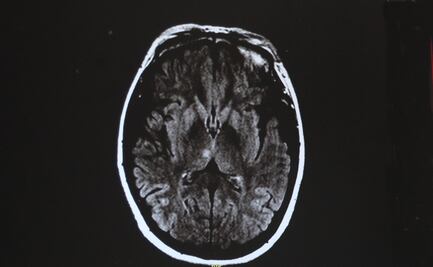

La curación de lesiones cerebrales podría relacionarse con un tipo de cáncer

Peter Dirks explicó que el glioblastoma puede considerarse "como una herida que nunca deja de curarse"